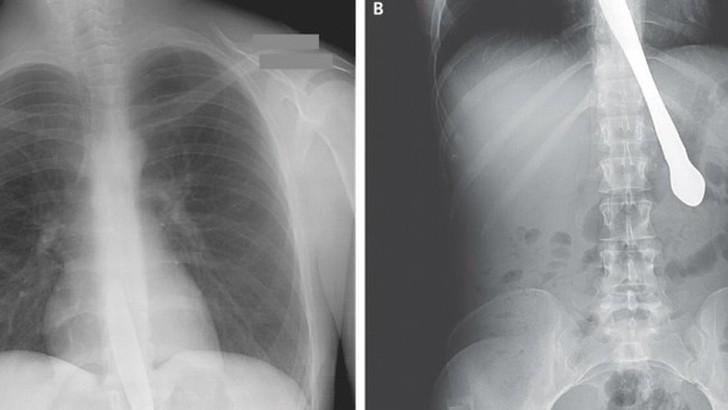

24. Ножницы.